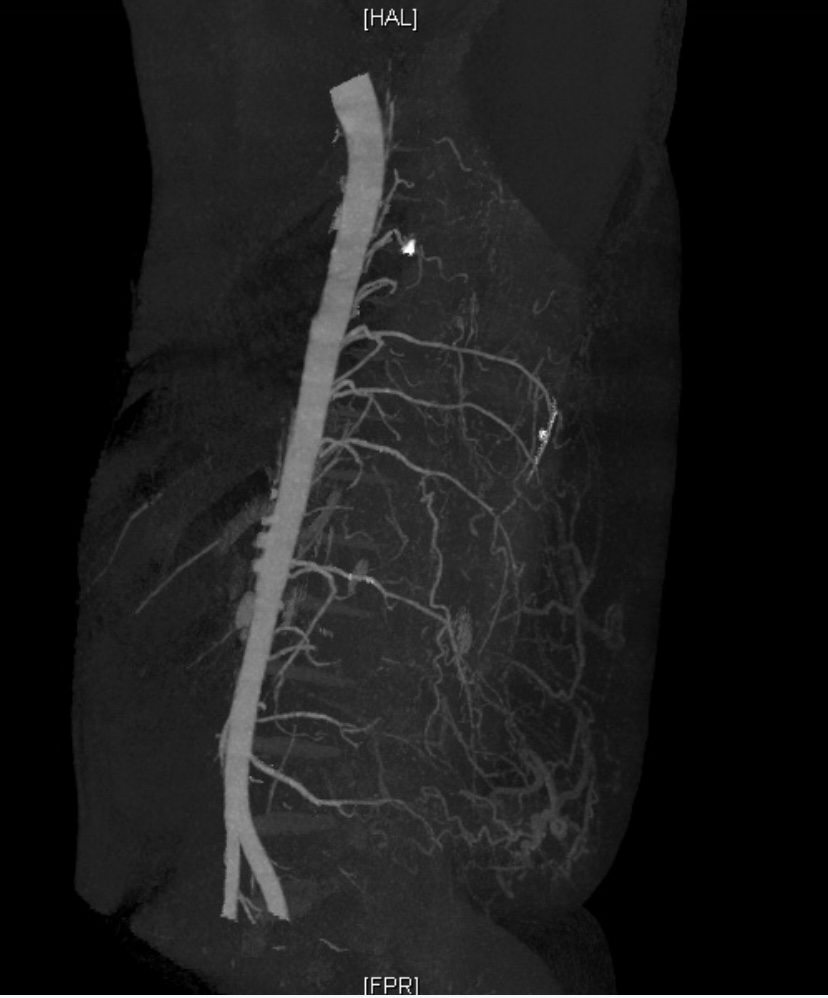

术前影像可见瘤体内多根供血血管及大量迂曲血管

“有效地减少出血和大面积创面植皮成活是手术重点。”杨建民说。为此,术前他带领团队做了充分准备:联合影像科、骨科及麻醉科等科室进行多学科讨论,确定手术方案,完善血管造影(CTA)、磁共振血管造影(MRA)等检查,明确瘤体的供血血管并在体表做好相应标记;与输血科联系备下充足的血和血浆,同时备好自体血回输准备,一旦意外发生,确保小郑的用血安全。“我们还制订了详细的游离修整皮瓣与植皮方案,减少二次创伤。通常情况下,这种手术需要7至8个小时。”杨建民补充道。